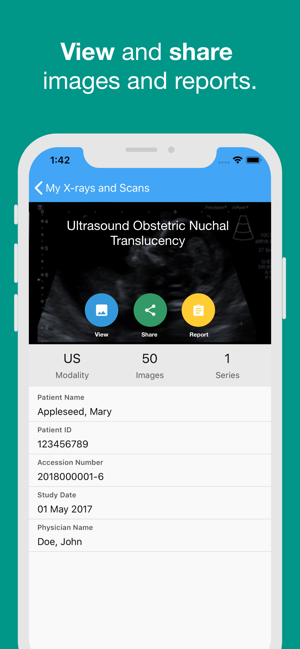

· access your images and reports (after your scan)

· share your results with family, friends or medical professionals

Once you have an account you can log in at any time to see your images and your reports. Your reports will be uploaded 14 days after we have authorised and sent the report to your referring doctor.